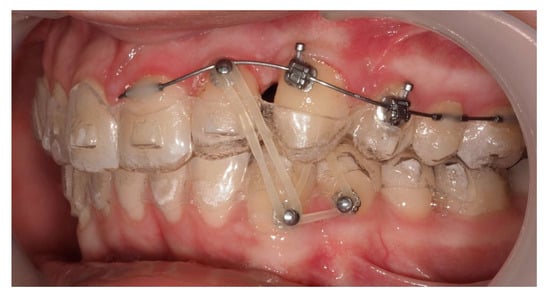

A 13-year-old male patient presented with Class II Division 2 malocclusion, a bilateral Class II sagittal relationship, and retroclined incisors. Cone-beam computed tomography revealed a palatally impacted maxillary left canine (tooth 23), with its cusp located palatally to the apical half of the left lateral incisor. The root exhibited significant apical curvature, extending toward the floor of the maxillary sinus (Figure 12 and Figure 13), making spontaneous eruption unlikely.

Figure 12.

Initial intraoral lateral photo.

An open surgical exposure was performed to access the crown of the IC. A button with a ligature wire was bonded and sealed using two layers of flowable composite resin, enabling controlled traction while minimizing the risk of debonding and simultaneously acting as a protective seal (Figure 14).

Figure 14.

Open surgical exposure of the canine with button fixation and ligature wire for subsequent traction.

Approximately 7 months later, a palatal mini-implant was placed between teeth 24 and 25, serving as stable anchorage for distal traction using an elastic chain, which was replaced monthly (Figure 15). This movement positioned the canine away from the lateral incisor root. Aligners were customized and adjusted throughout treatment.

Figure 15.

Adjusted aligners, palatal mini-implant, and elastic chain used for distalizing the canine; 7 months after the surgery.

Following initial distalization, a sectional fixed appliance was bonded from tooth 11 to 26. On tooth 24, a bracket with a metallic ligature was used to support Class II elastics. Mini-tubes were bonded on teeth 22, 25, and 26, and the aligners were trimmed accordingly (Figure 16). A ligature wire connected the palatal button on the canine to a 0.014” nitinol archwire (Figure 17).

Figure 16.

Sectional fixed appliance from teeth 11 to 26, with support for Class II elastics to improve sagittal relationship; 14 months after the surgery.

Figure 17.

Ligature wire attached to a 0.014” nitinol archwire on the palatal surface of the canine; 14 months after the surgery.

During vestibular traction, gingival removal was required. The canine presented mesial tipping and rotation. In the 14th month after the surgery, a bracket was bonded to tooth 23, following its inclination. A button was bonded on tooth 33 and connected by elastic to tooth 22 to stabilize the vertical position. Another elastic with a Class II vector was attached from the bracket on tooth 24 to a precision cut in the lower aligner (Figure 18).

Figure 18.

Vestibular traction of the canine, gingival removal, and elastic use for vertical stabilization; 14 months after the surgery.